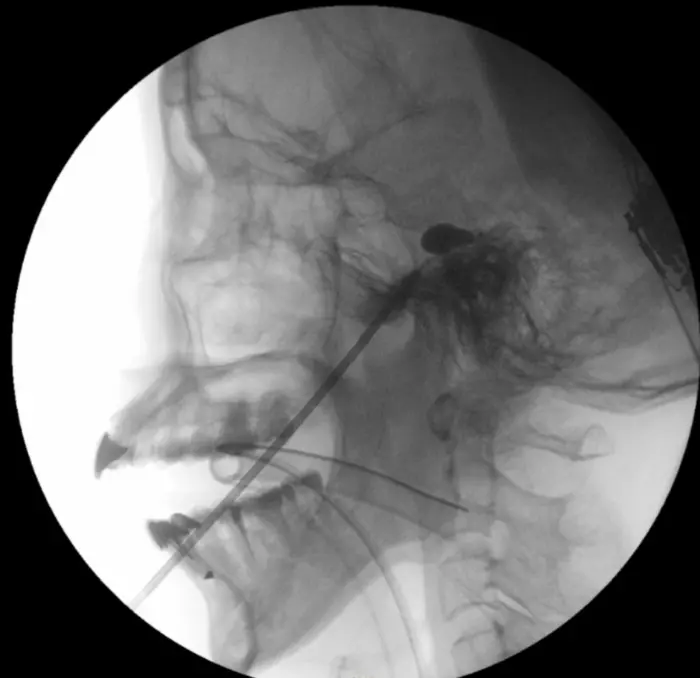

PBC is an interventional technique that alleviates pain by inserting a small balloon into the trigeminal ganglion near the base of the skull and inflating it to compress the nerve’s pain fibres.